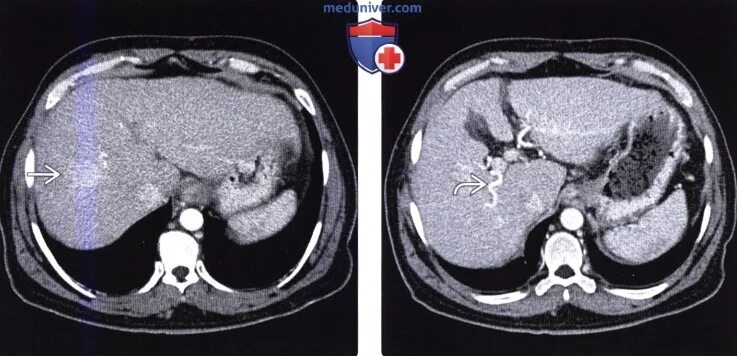

Цирроз печени кт